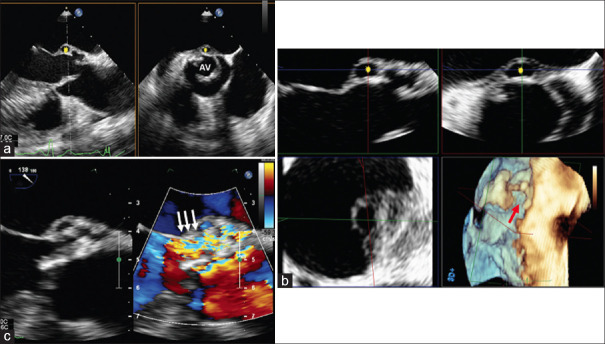

A unicuspid aortic valve (UAV) in adults is a very rare form of aortic valve (AV) malformation. UAV has two distinct subtypes, acommissural UAV and unicommissural, and can be differentiated by anatomical features, imaging modalities, and clinical presentation. With the development of significant AV lesion (s), surgical or transcatheter intervention will be required. The first part is a summarized review of UAV (anatomical features, clinical presentation, diagnostic modalities, and management). In the second part, we present a series of four patients diagnosed with UAV (3 unicommissural and 1 acommissural). The first case underwent balloon aortic valvuloplasty during childhood and surgical AV replacement later, with the progression to severe aortic stenosis (AS). The second case underwent a Ross procedure. The third and fourth cases were asymptomatic with moderate AS and mild-to-moderate AR and were kept on follow-up. In all the cases, transesophageal echocardiography confirmed the diagnosis of UAV with detailed morphological and functional assessment of AV.